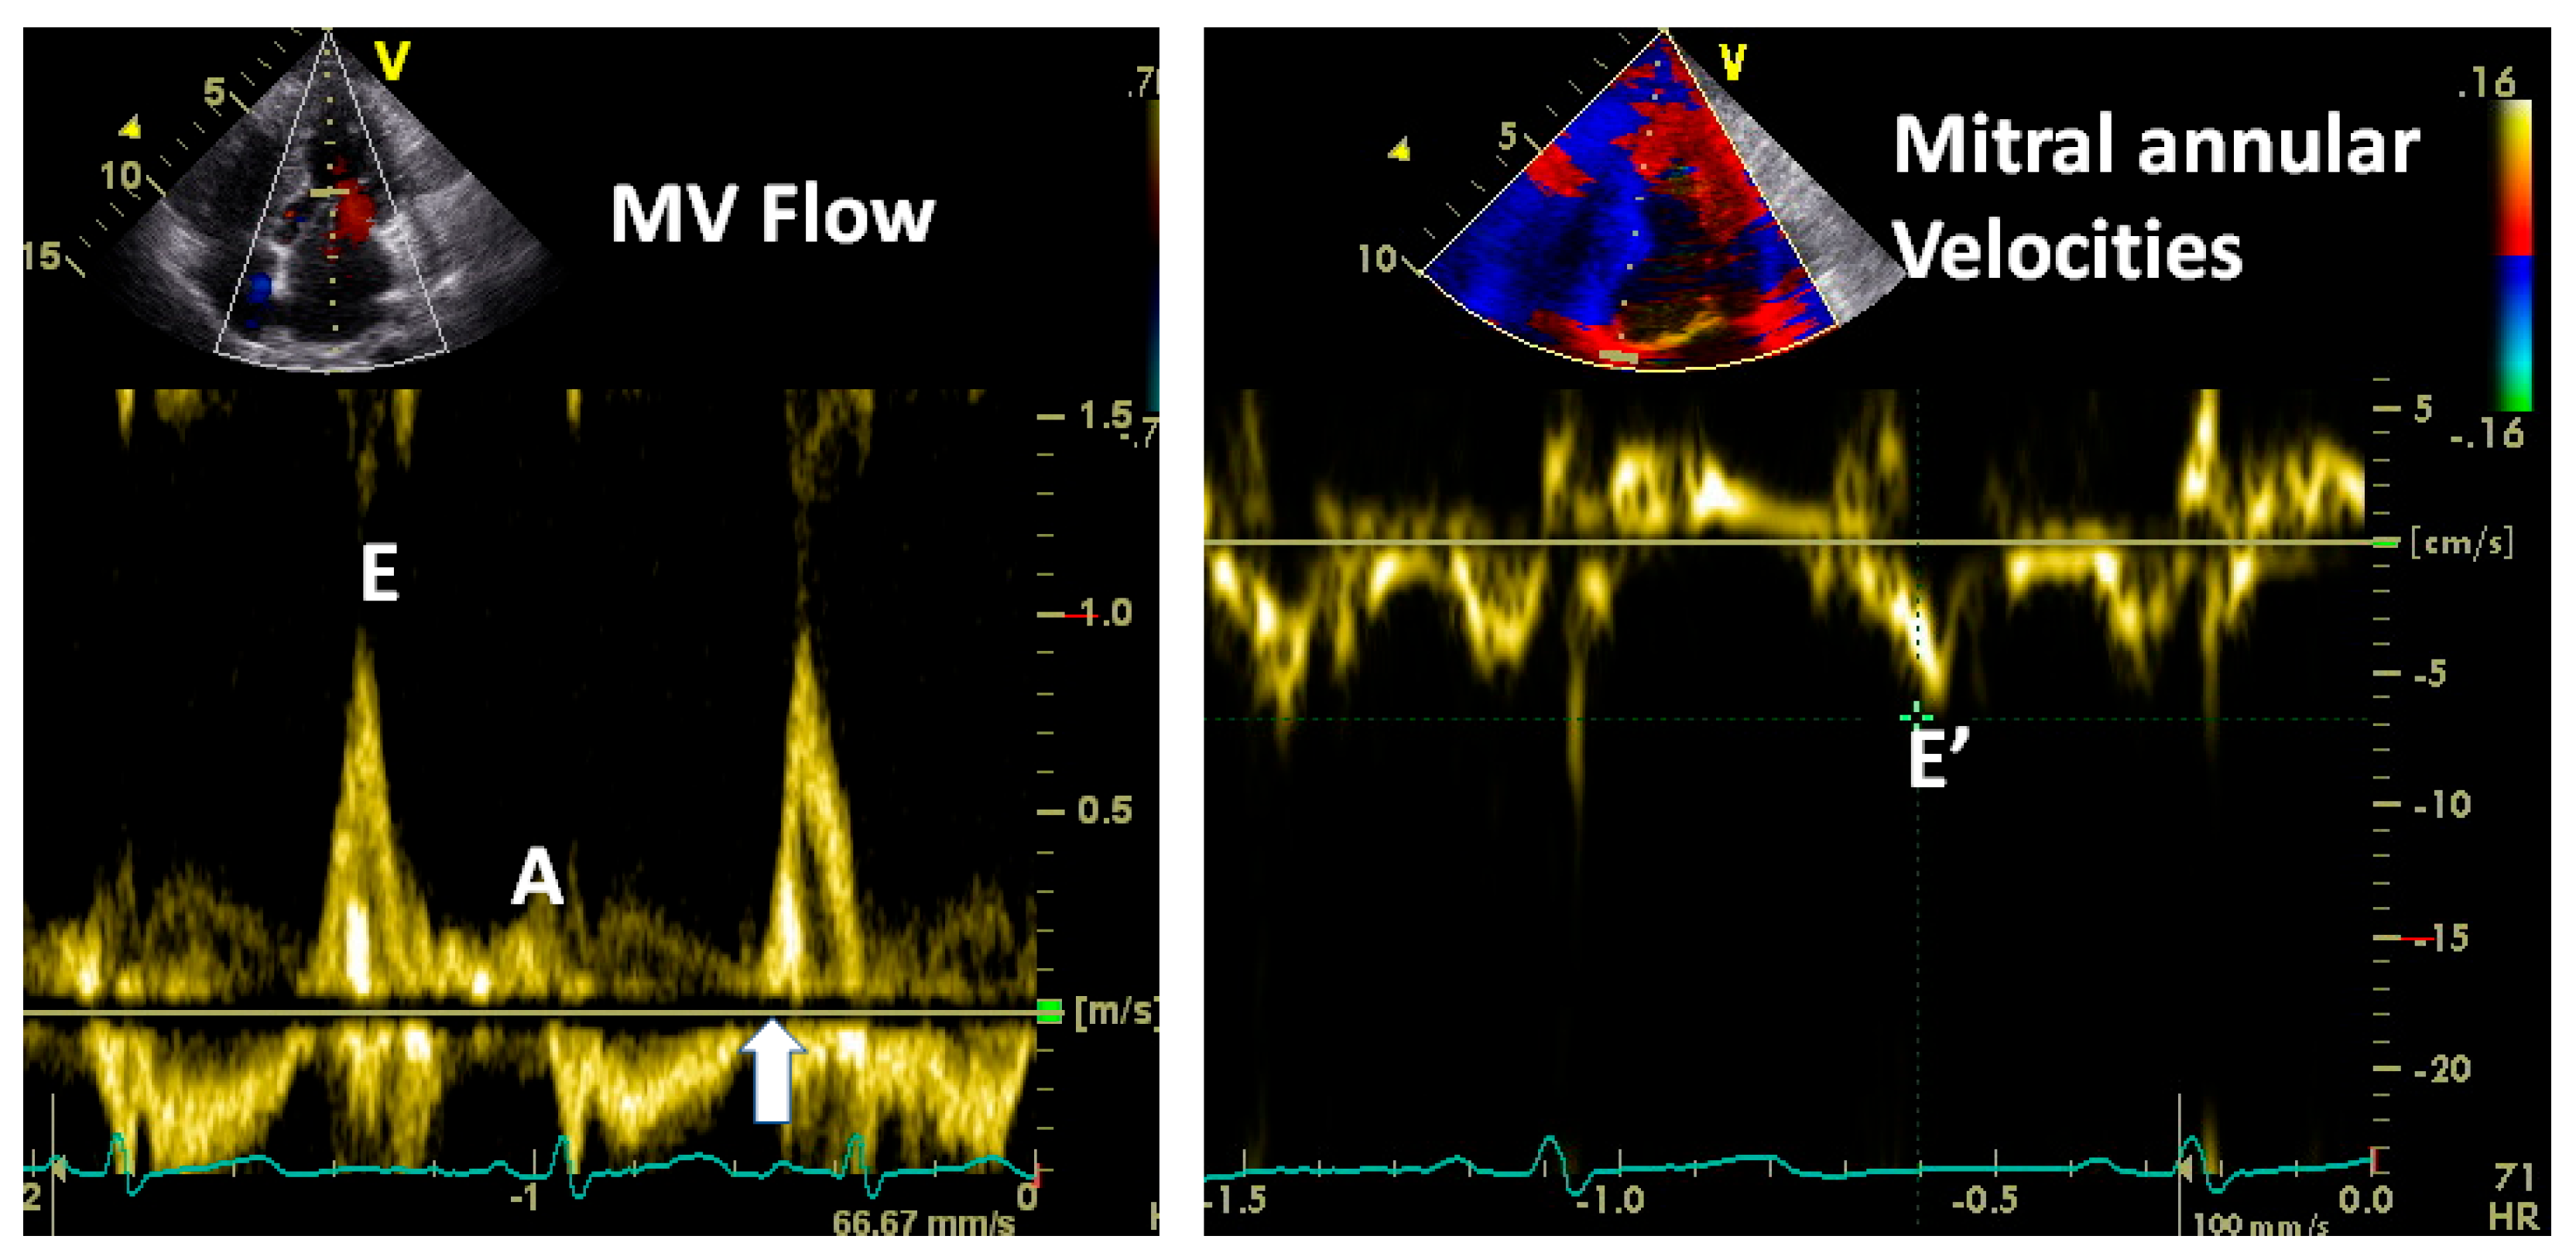

3.2.1. Transmitral Flow

| Factors affecting E wave amplitude: |

| Impaired LV relaxation reduces E wave amplitude |

| High LA pressure increases its amplitude |

| Exaggerated LV recoil increases its amplitude |

| Factors affecting mitral A wave amplitude: |

| Left atrial contractile function: reduced in atrial cardiomyopathy, post cardioversion |

| Atrial preload: larger LA volume at the time of systole boosts the atrial transport function |

| Atrial afterload: Higher LVEDP or pre-A pressure will reduce atrial contribution |